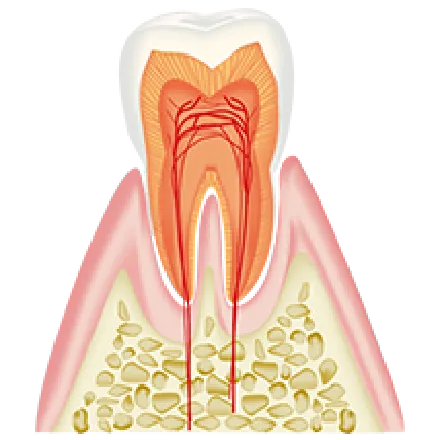

健康な歯

濃いピンク色の引き締まった

歯肉で、歯磨きでも出血しない